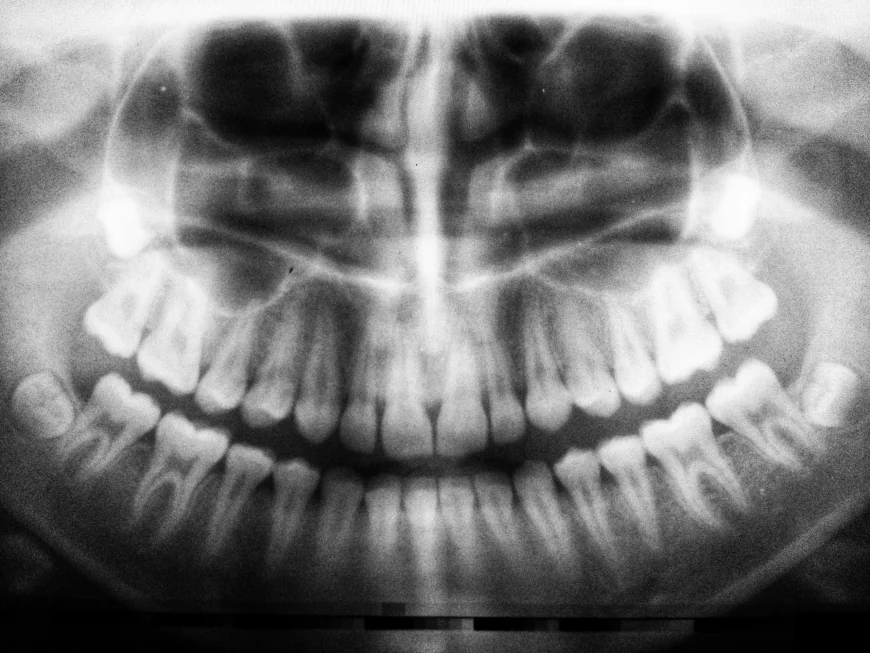

A panoramic dental X-ray is a modern diagnostic tool that gives a full view of your teeth, jaws, and surrounding structures in a single image. Unlike traditional X-rays that only capture a small section, this method provides a complete overview, making it easier for dental professionals to identify hidden concerns. For individuals curious about Panoramic Dental X-Ray Cost in Dubai, it is natural to also want to understand what happens during such a visit and how it can benefit their oral health journey.

A panoramic dental X-ray is designed to give a wide-angle view of your mouth in just a few seconds. This type of imaging helps in diagnosing dental issues such as impacted teeth, jaw disorders, bone abnormalities, and even early signs of oral diseases. It plays a vital role in treatment planning, especially for orthodontic work, implants, and wisdom tooth extraction. Knowing its purpose ahead of time prepares you for the importance of this step during your dental visit.

Many dental concerns are not visible to the naked eye. Panoramic imaging allows professionals to detect hidden issues before they progress into bigger problems. For instance, early signs of bone loss, infections, or tumors can be detected through this scan. It also helps in evaluating growth patterns in children and teenagers, making it a valuable tool for monitoring oral health at all ages. By offering a comprehensive view, it reduces the need for multiple separate X-rays, saving both time and effort.

Once the panoramic image is taken, it will be carefully reviewed to create or update your treatment plan. The results are usually available instantly, and the clear, detailed image helps in discussing next steps. Patients often appreciate how easy it is to understand the visuals, since the full mouth view is straightforward and less confusing compared to multiple small images. This clarity helps in building confidence when making decisions about upcoming treatments.